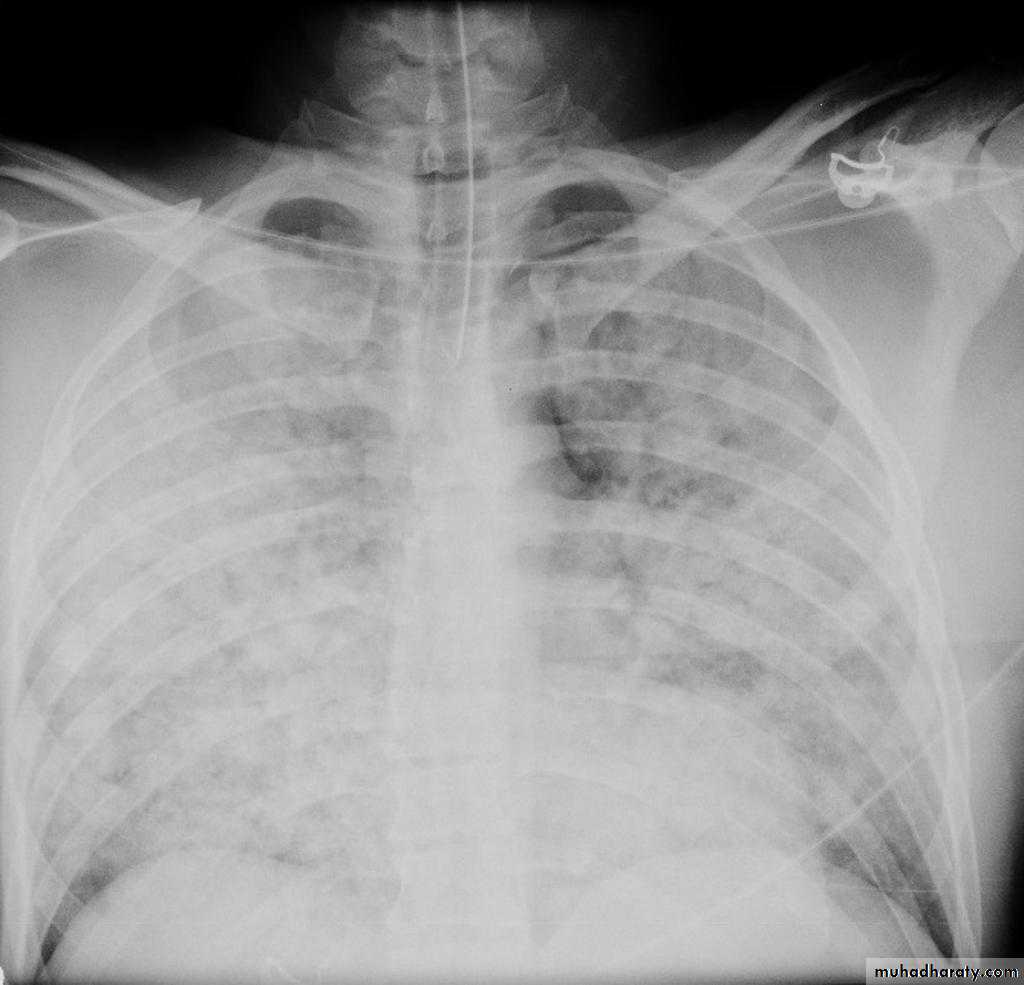

Pulmonary edema is a broad descriptive term and is usually defined as an abnormal accumulation of fluid in the extra-vascular compartments of the lung .

Radiographic features

Septal lines, also known as Kerley lines, are seen when the interlobular septa in the pulmonary interstitium become prominent. This may be because of lymphatic engorgement or edema of the connective tissues of the interlobular septa. They usually occur when pulmonary capillary wedge pressures reach 20-25 mmHg ,

Classification

Kerley A linesThese are 2-6 cm long oblique lines that are <1 mm thick and course towards the hila. They represent thickening of the interlobular septa

Kerley B lines

These are 1-2 cm thin lines in the peripheries of the lung. They are perpendicular to and extend out to the pleural surface . They represent thickened sub pleural interlobular septa and are usually seen at the lung bases.Interstitial pulmonary edema

radiograph include if pressure > 25 mmHg the findings of :

cardiac size/cardio-thoracic ratio: useful for assessing for an underlying cardiogenic cause or associationbat wing pulmonary opacities

presence of peri-bronchial cuffing

septal lines: Kerley lines become more prominent

pleural effusions

pulmonary venous engorgement/pulmonary blood flow distribution upper lobe pulmonary venous diversion

Alveolar pulmonary edema